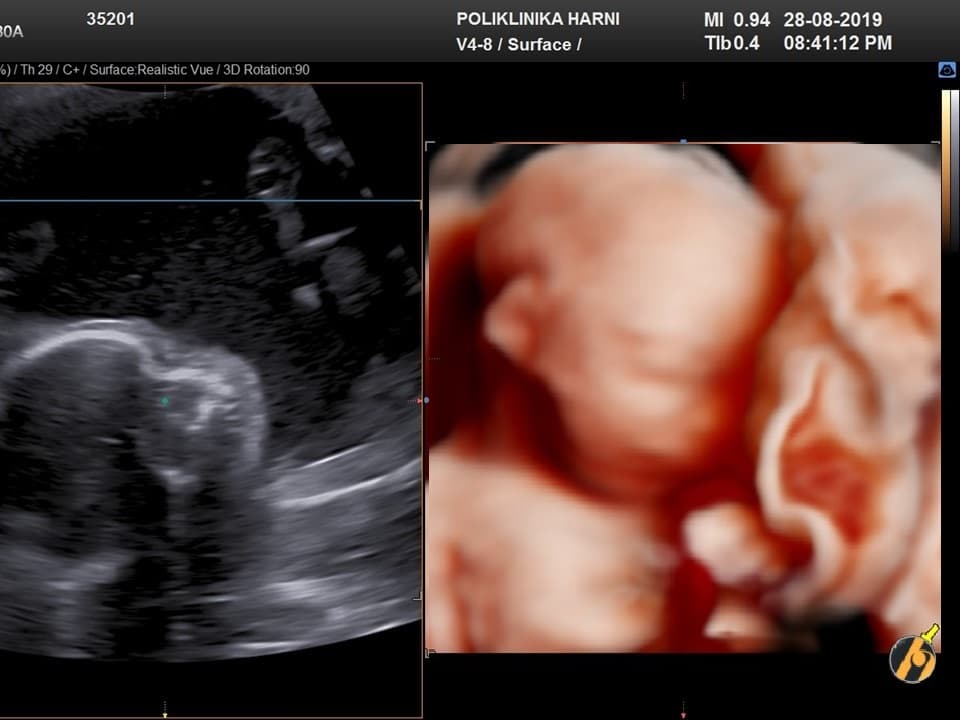

Zahvaljujući intenzivnom razvoju mišića i kostiju, sve su češći fetalni pokreti. Beba uspravlja glavu, ali može i žmirkati, otvarati usta ili se mrštiti jer napreduje i razvoj muskulature lica. Trudnica koja je već rađala počinje osjećati fetalne pokrete u ovom tjednu, dok trudnice koje su po prvi puta ostvarile trudnoću počinju osjećati fetalne pokrete kasnije, obično u 20.tjednu. Fetalne pokrete kasnije osjećaju i trudnice s viškom kilograma, pošto masno tkivo djeluje kao izolator.

Vaša beba dugačka je sveukupno 14 - 16 cm, a teška 80 - 120 g, često se uspoređuje s veličinom avokada.